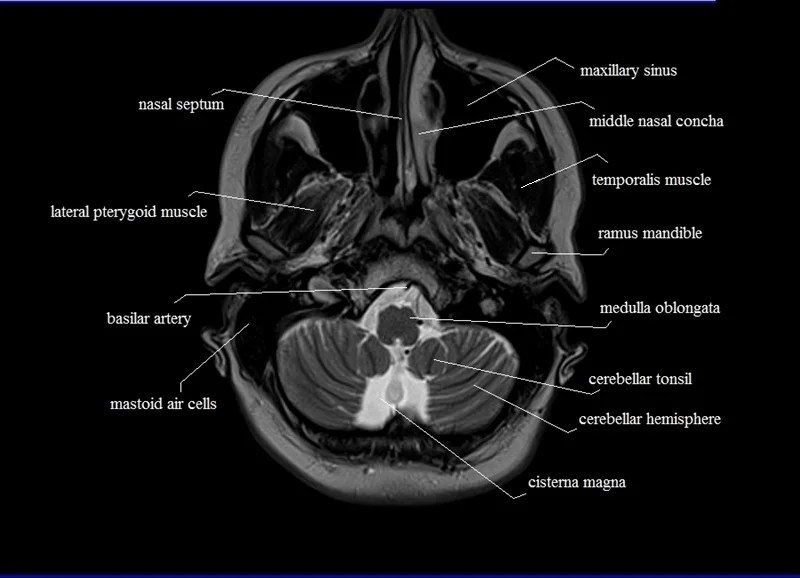

MRI anatomy Free MRI Axial Brain Anatomy Mri Anatomy Axial Note, however, that mcrae’s line (basion. A brain mri is one of the most commonly performed techniques of medical imaging. The anatomy of the brain is studied by means of axial, coronal and sagittal views. Mri axial cross sectional anatomy of brain. The mri sequence used is a 3d gradient. It is the most complete reference of human anatomy available.. Mri Anatomy Axial.